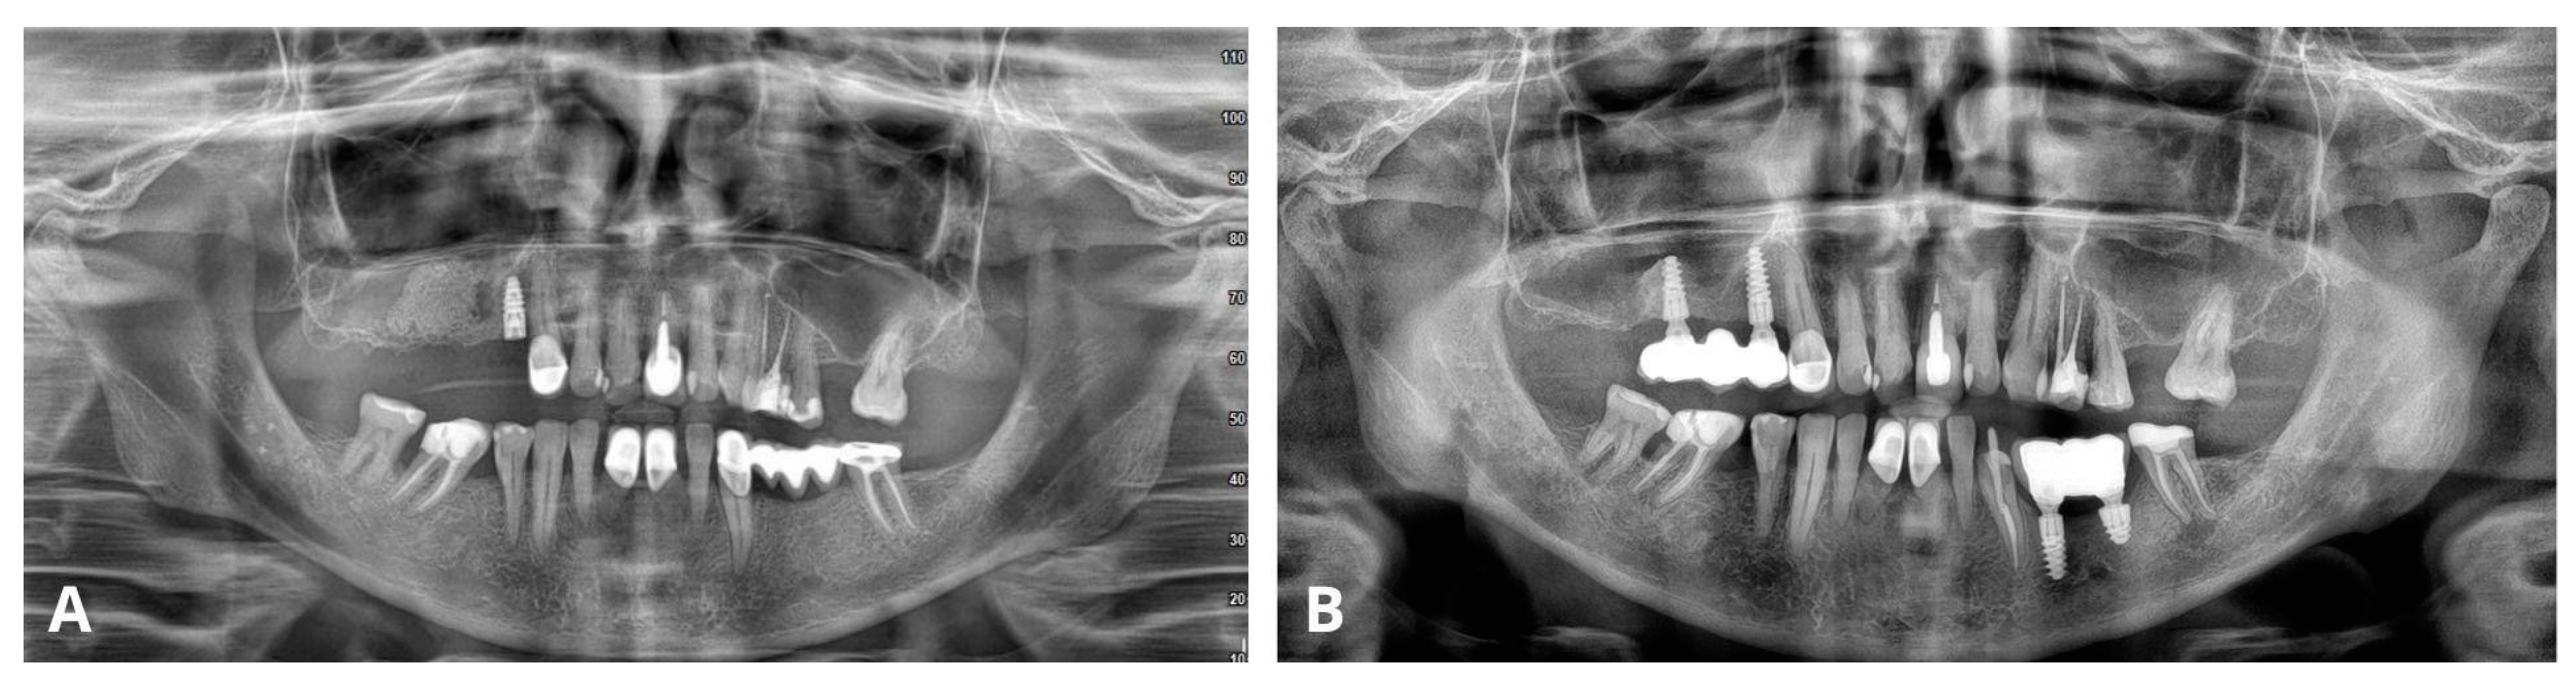

The last figure (Figure 20) compares OPG radiographs after the procedure and 4 years after the patient received the bridge on implants, showing no recurrence of the cyst and stable implants with prosthetic reconstruction.

Figure 20. Comparison of orthopantomogram (OPG) immediately after the procedure (A) and 4 years after delivering the final reconstruction on implants (B).